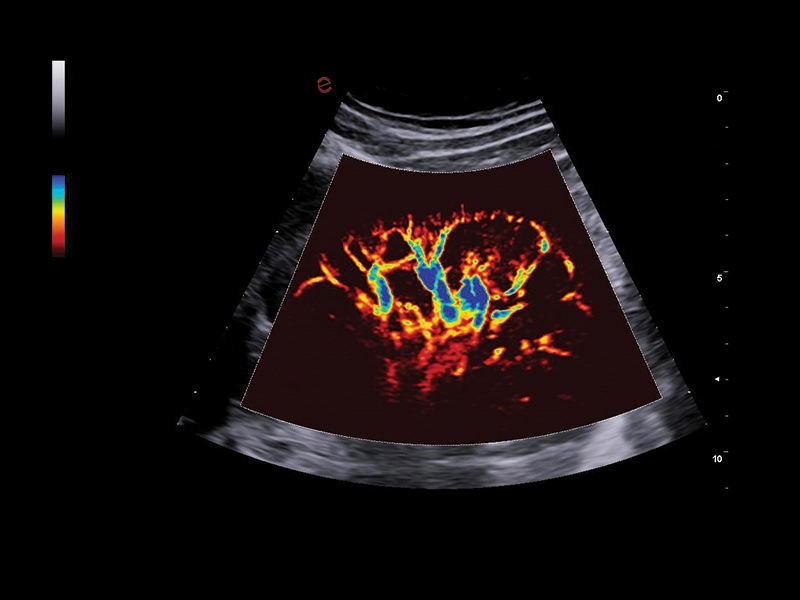

MyLab™9 Platform - XFlow Doppler enhancement in liver vascularization

MyLab™9 Platform - XFlow Doppler enhancement in liver vascularization